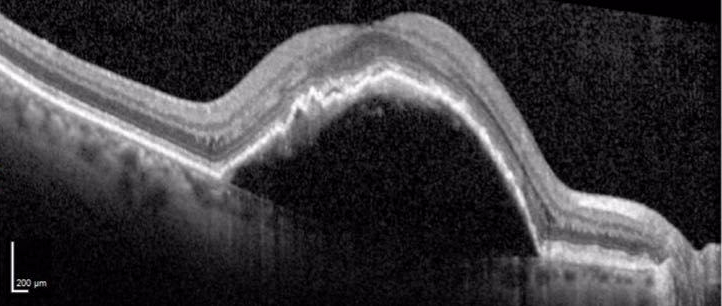

Figure: Heidelberg Spectralis spectral domain optical coherence tomography image of the right eye. All scans are horizontal foveal scans. A) One month prior to development of pigment epithelial detachment (PED), drusen are apparent. B) Development of large PED, maximum vertical dimension 289 μm. C) After three monthly intravitreal aflibercept injections., the PED was significantly increased with a maximum vertical PED dimension 630 μm. D) One month after intravitreal 0.7 mg dexamethasone implant (OZURDEX) combined with repeat intravitreal aflibercept injection, the PED resolved. Visual acuity remained 20/64.